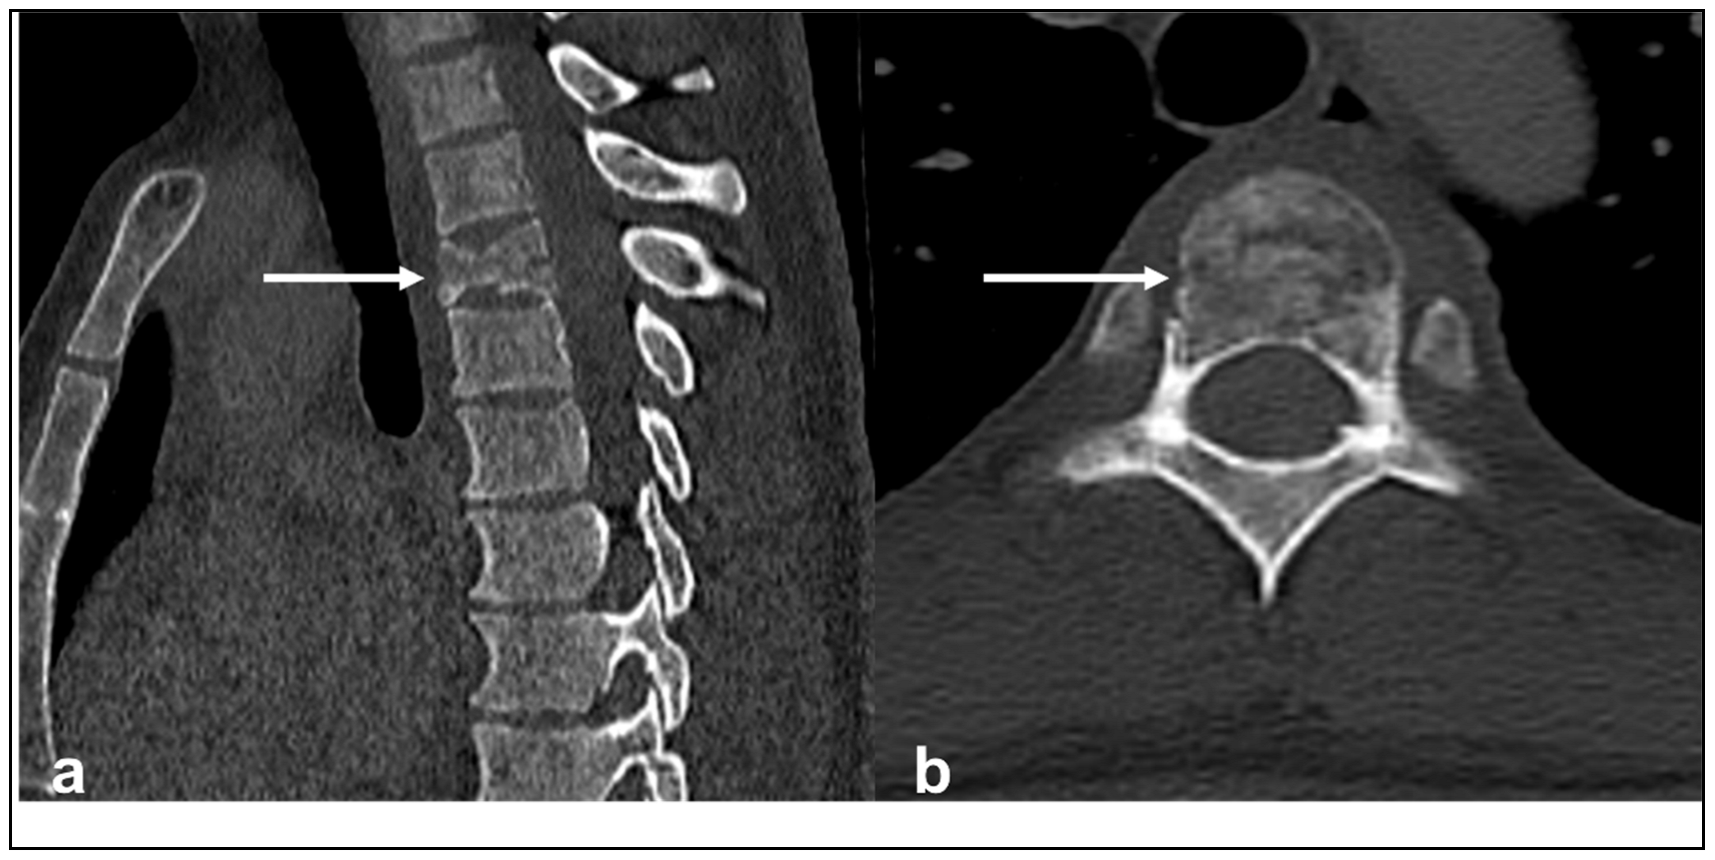

| Chondrosarcoma | Lytic lesion. ‘Rings and arcs’ calcification characteristic of chondroid matrix. | High T2 signal due to cartilage and myxoid content. Peripheral and septal enhancement. Enhancing extra-osseous soft tissue component. |